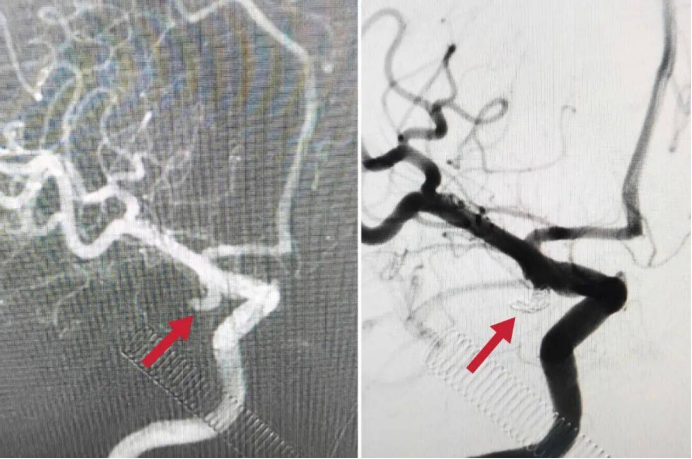

该患者由外院转诊而来,入院时已出现嗜睡、剧烈头痛、呕吐等危急症状,头部CT检查显示其存在广泛蛛网膜下腔出血,病情凶险,随时可能因动脉瘤再次破裂危及生命。面对复杂病情,经开院区神经外科团队迅速响应,联合多学科专家紧急会诊,结合患者病情制定了周密的介入栓塞手术方案。

手术过程中,各科室紧密协作:急诊科快速完成预检分诊与急救处理,为后续治疗争取宝贵时间;放射科精准的影像学检查为手术方案制定提供关键依据;检验科高效完成术前各项检验,保障手术安全;麻醉科团队全程密切监测患者生命体征,确保麻醉深度适宜;手术室医护人员默契配合,为手术顺利进行提供有力支持;术后患者被转入重症医学科,接受精细化监护与治疗,为康复奠定良好基础。